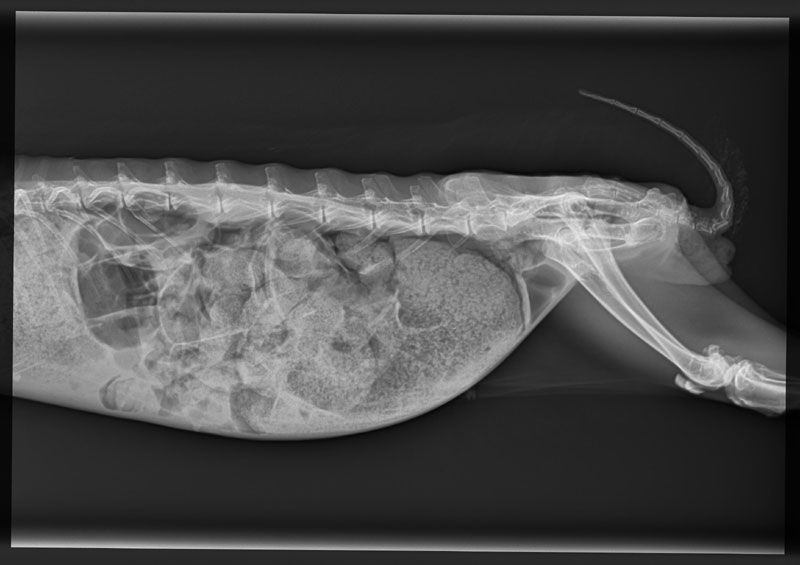

- Digitale Röntgen-Diagnostik